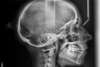

Béance traitée par gouttières

Début du traitement